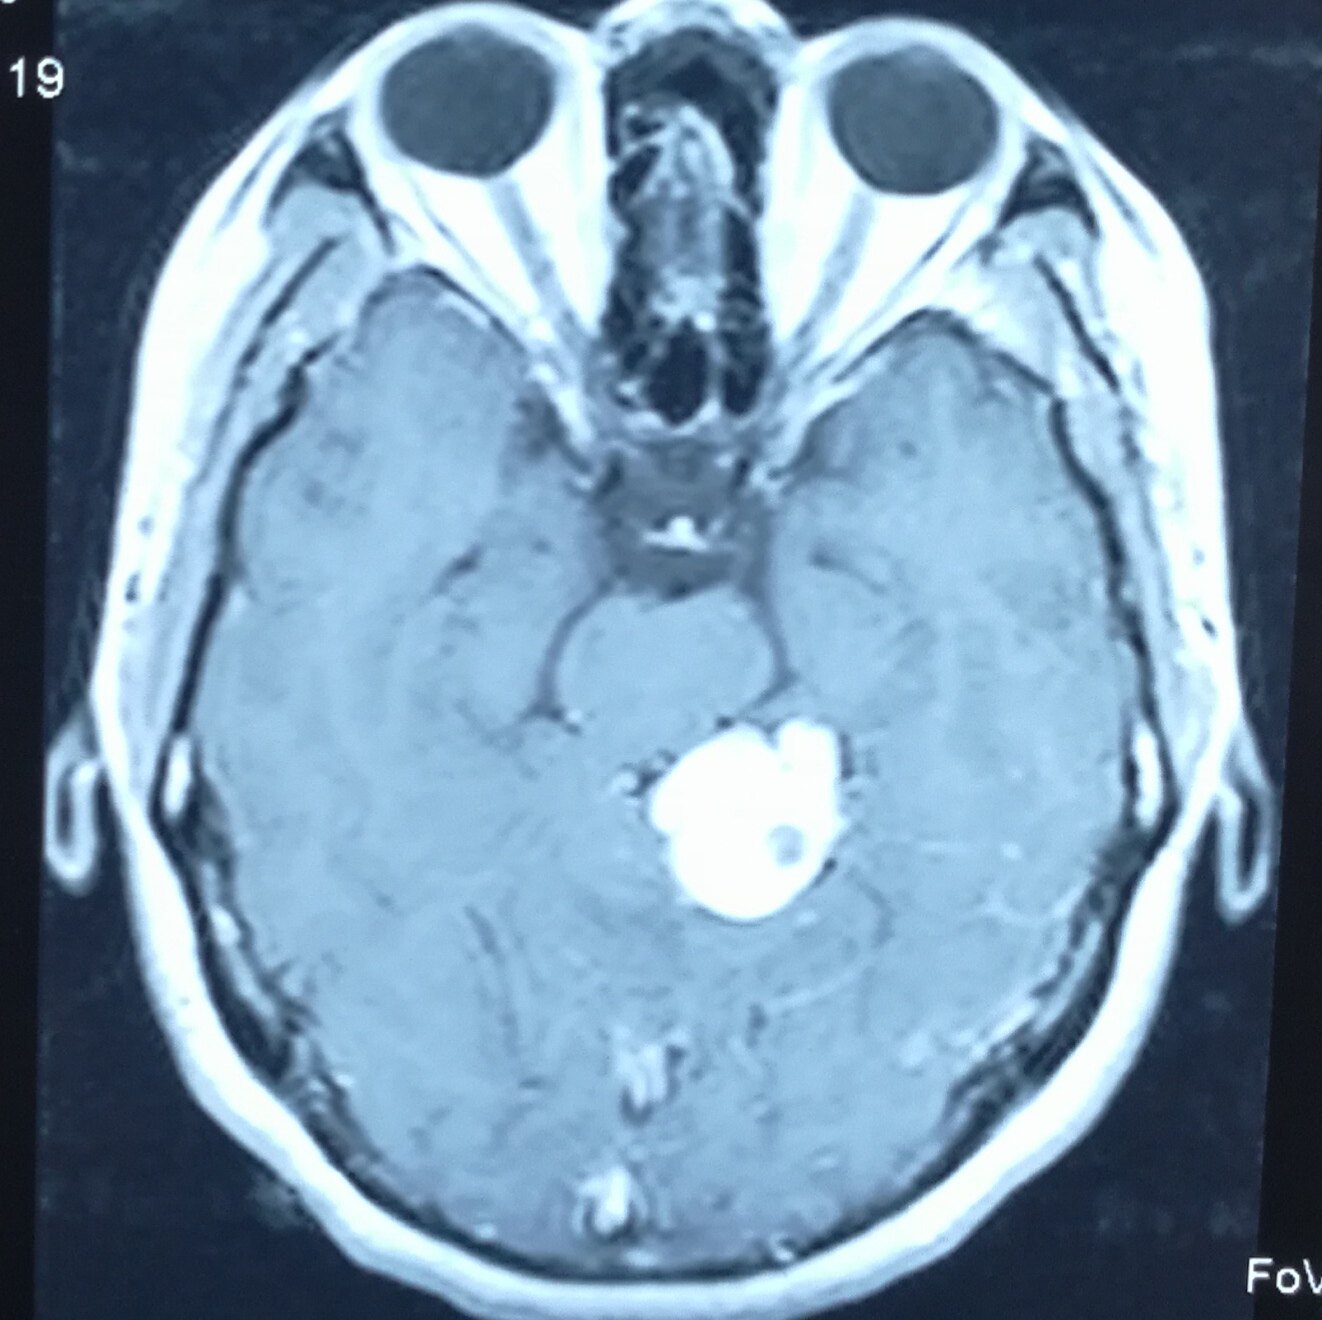

颅内少见肿瘤,约占颅内肿瘤的1%~2%,幕下肿瘤的7%,血管母细胞瘤又称血管网状细胞瘤,是真性血管性肿瘤,

血管母细胞瘤是由脑神经和脊髓神经所产生的一种高度血管分化的良性肿瘤。大多数的血管母细胞瘤是由单一病灶

脑血管母细胞瘤也称毛细血管血管瘤、血管内皮瘤、血管外皮瘤、Lindau瘤和血管网状细胞瘤。脑血管母细胞瘤为